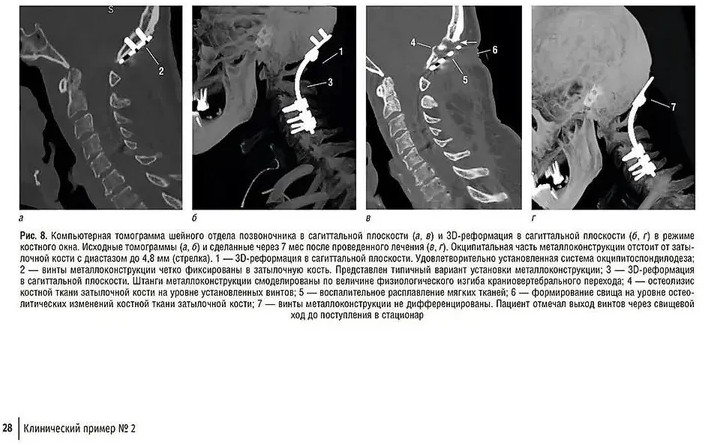

💳 Оплатить за товар можно при получении 🇰🇿 Есть бесплатная доставка по Казахстану от 1 дня 🎁 Копите бонусы с каждой покупки В руководстве впервые в отечественной научной литературе представлен подробный иллюстративный материал, касающийся различных гнойно-воспалительных патологий всех отделов позвоночника в корреляции с клинико-лабораторной картиной. Это уникальное издание содержит подробные описания, компьютерные и магнитно-резонансные томограммы различных заболеваний позвоночника, вызванных бактериальной инфекцией. Особое внимание уделено описанию симптомов, причин и методов лечения этих заболеваний, пониманию особенности каждого гнойно-воспалительного процесса в позвоночнике, что позволит принимать обоснованные решения при диагностике заболеваний и лечении пациентов. |